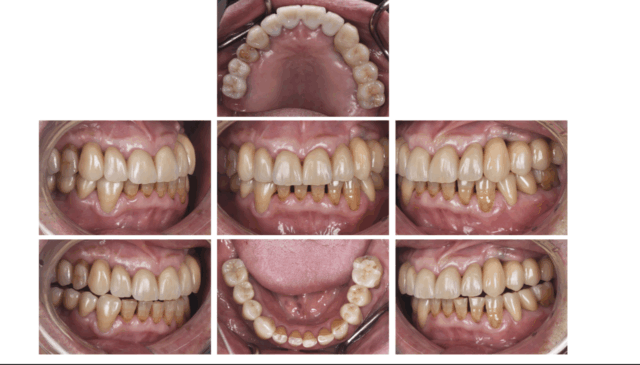

Before

After